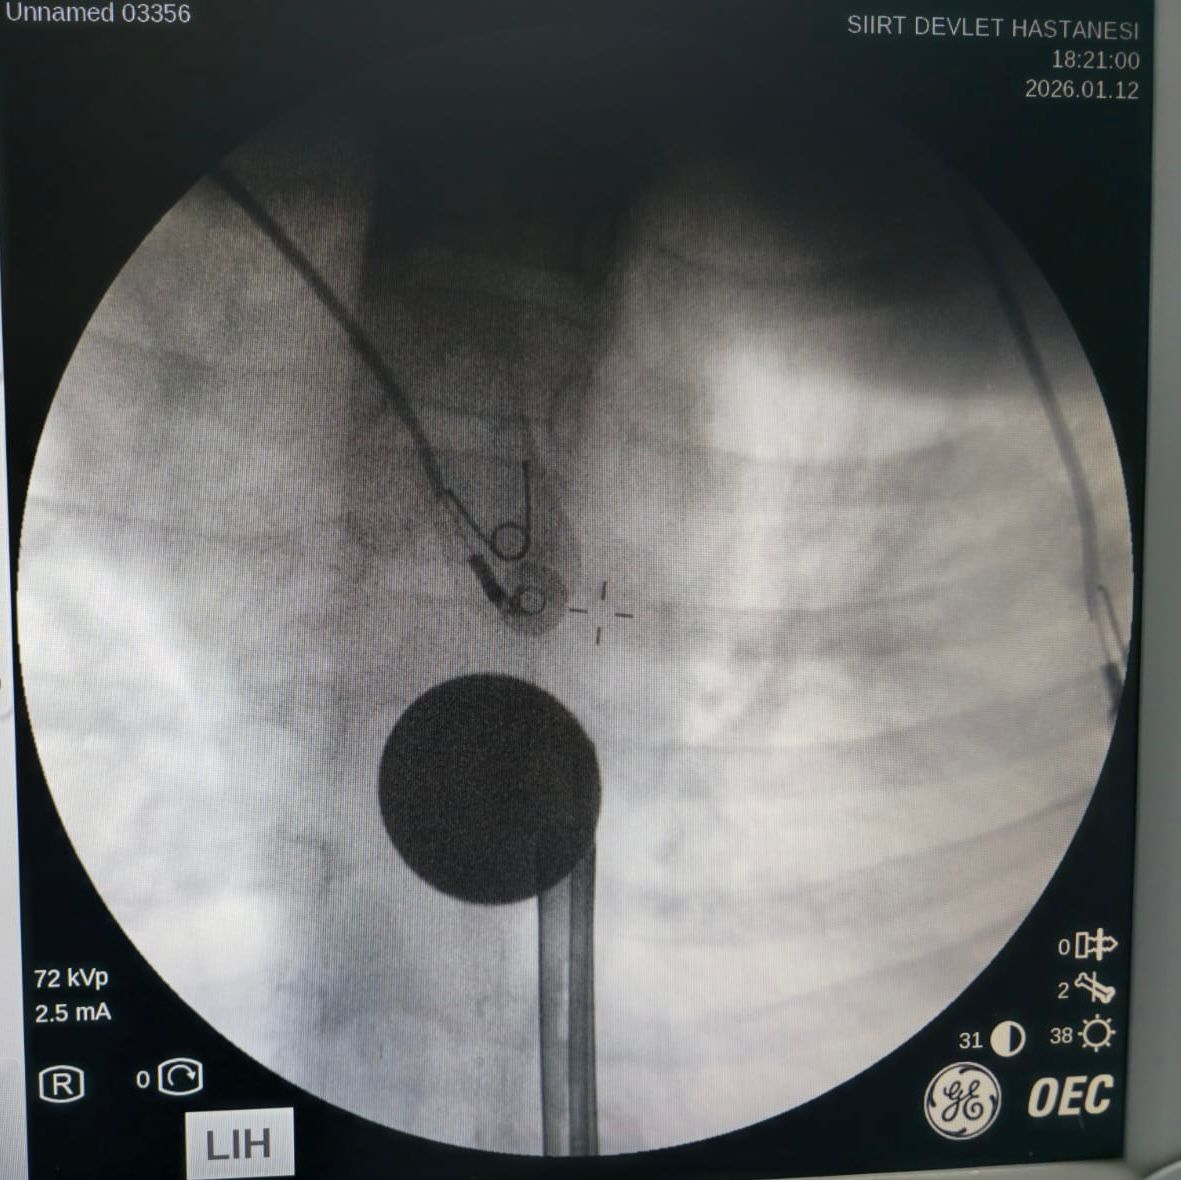

Edinilen bilgilere göre, yabancı cisim yutma şikâyetiyle hastaneye başvuran küçük hasta, yapılan ilk değerlendirme ve görüntüleme tetkiklerinin ardından ilgili branşlar tarafından operasyona alındı. Y.K.’nin yemek borusuna kadar ilerlediği tespit edilen madeni paranın çıkarılması için Gastroenteroloji Uzmanı Dr. Yaren Dirik ile Kulak Burun Boğaz (KBB) Hekimi Dr. Yasin Gökçınar tarafından ortak bir girişim gerçekleştirildi.

Siirt Eğitim ve Araştırma Hastanesi Başhekim Yardımcısı Uzman Dr. Burak Özkan, konuya ilişkin yaptığı açıklamada çocuk hastalarda yabancı cisim yutma vakalarının ciddi riskler oluşturabileceğine dikkat çekerek, “Hastanemize başvuran 8 yaşındaki hastamızın yemek borusuna kaçan madeni para, gastroenteroloji ve KBB ekiplerimizin koordineli ve titiz çalışmasıyla herhangi bir komplikasyona yol açmadan başarılı bir şekilde çıkarılmıştır. Operasyon süreci sorunsuz geçmiş olup hastamızın genel durumu iyidir,” ifadelerini kullandı.